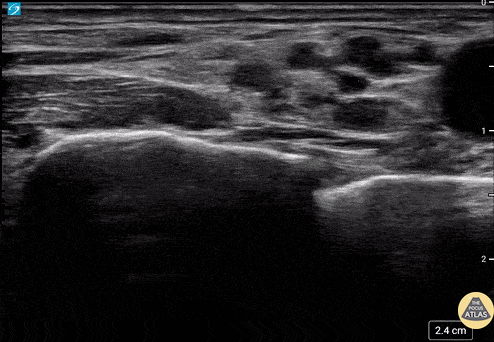

Anatomy for a supraclavicular brachial plexus block. Tom Jelic @tomjelic

https://www.thepocusatlas.com/nerve-blocks-gallery